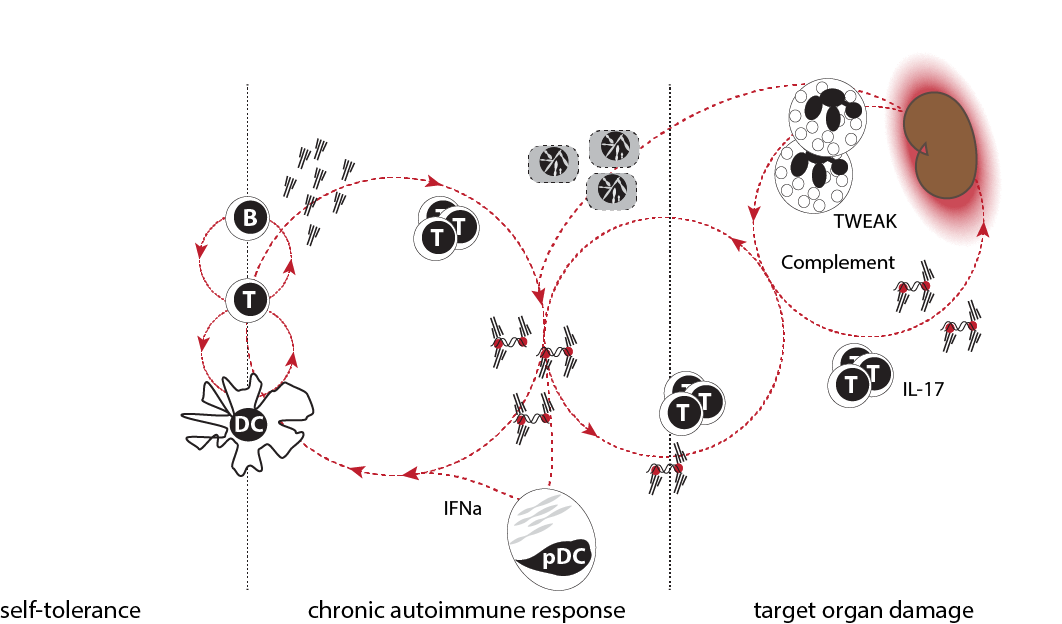

PatogĂŠnesis de lupus en tres fases. Las respuestas inmunes se controlan en forma estricta y las pĂŠrdidas de tolerancia suelen ser transitorias en individuos sanos. Los pacientes con lupus desarrollan en forma gradual una respuesta autoinmune crĂłnica que se manifiesta por la producciĂłn constante de autoanticuerpos y activaciĂłn inmune. El significado clĂnico de dicha respuesta es desconocido. En algunos pacientes, productos de la respuesta autoinmune crĂłnica pueden provocar inflamaciĂłn en Ăłrganos blanco. Los factores que permiten la pĂŠrdida de tolerancia y el inicio de la inflamaciĂłn, probablemente son diferentes. Asimismo, las vĂas patogĂŠnicas involucradas en la segunda y tercera fases son probablemente diferentes